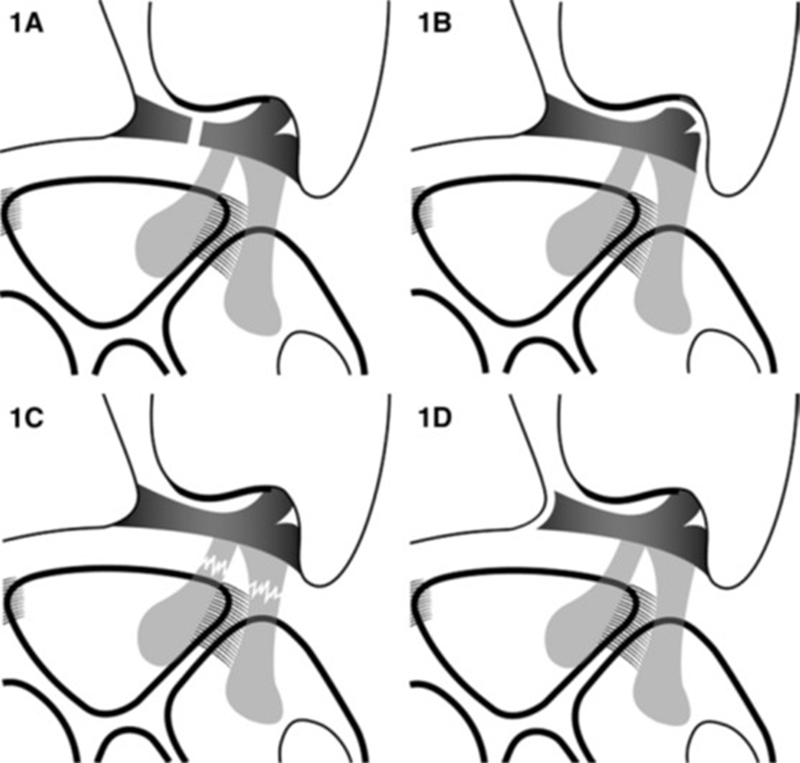

Ⅰ类:创伤性损伤

A:中心穿孔

B:尺侧撕裂(伴尺骨茎突骨折/不伴尺骨茎突骨折)

C:远端撕裂

D:桡侧撕裂

多发生在手腕过度伸展加上扭转的动作下,在远端尺骨处的手腕尺侧(小拇指侧)遭受外力的冲击。